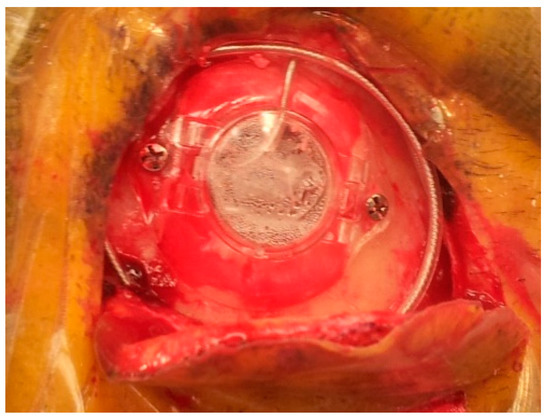

After identification of the STN borders and depth by the MER, we started high-frequency macrostimulation. The aim of the stimulation was to confirm the optimal target, which provided adequate control of the Parkinsonian symptoms (specifically tremors), without undesirable effects from stimulation below 4 volts. Once we reached our desired target, we removed the microelectrode and replaced it with a standard four-contact (0–3) deep brain stimulation electrode (Medtronic DBS lead 3389). Generally, we placed the deepest electrode contact (0) at or just beyond the target point. We repeated the testing using this electrode in order to confirm the reproducibility of the effects. We locked the electrode in place using a Stimloc device (Medtronic, Minneapolis, MN, USA) (Figure 12). The excess of the electrode was coiled around the burr hole to create a strain relief loop (Figure 13). Then the same procedure was repeated on the right side.

Figure 13. The final appearance of the electrode fixed using the Stimloc device; the excess of the electrode is coiled around the burr hole to create a strain relief loop.